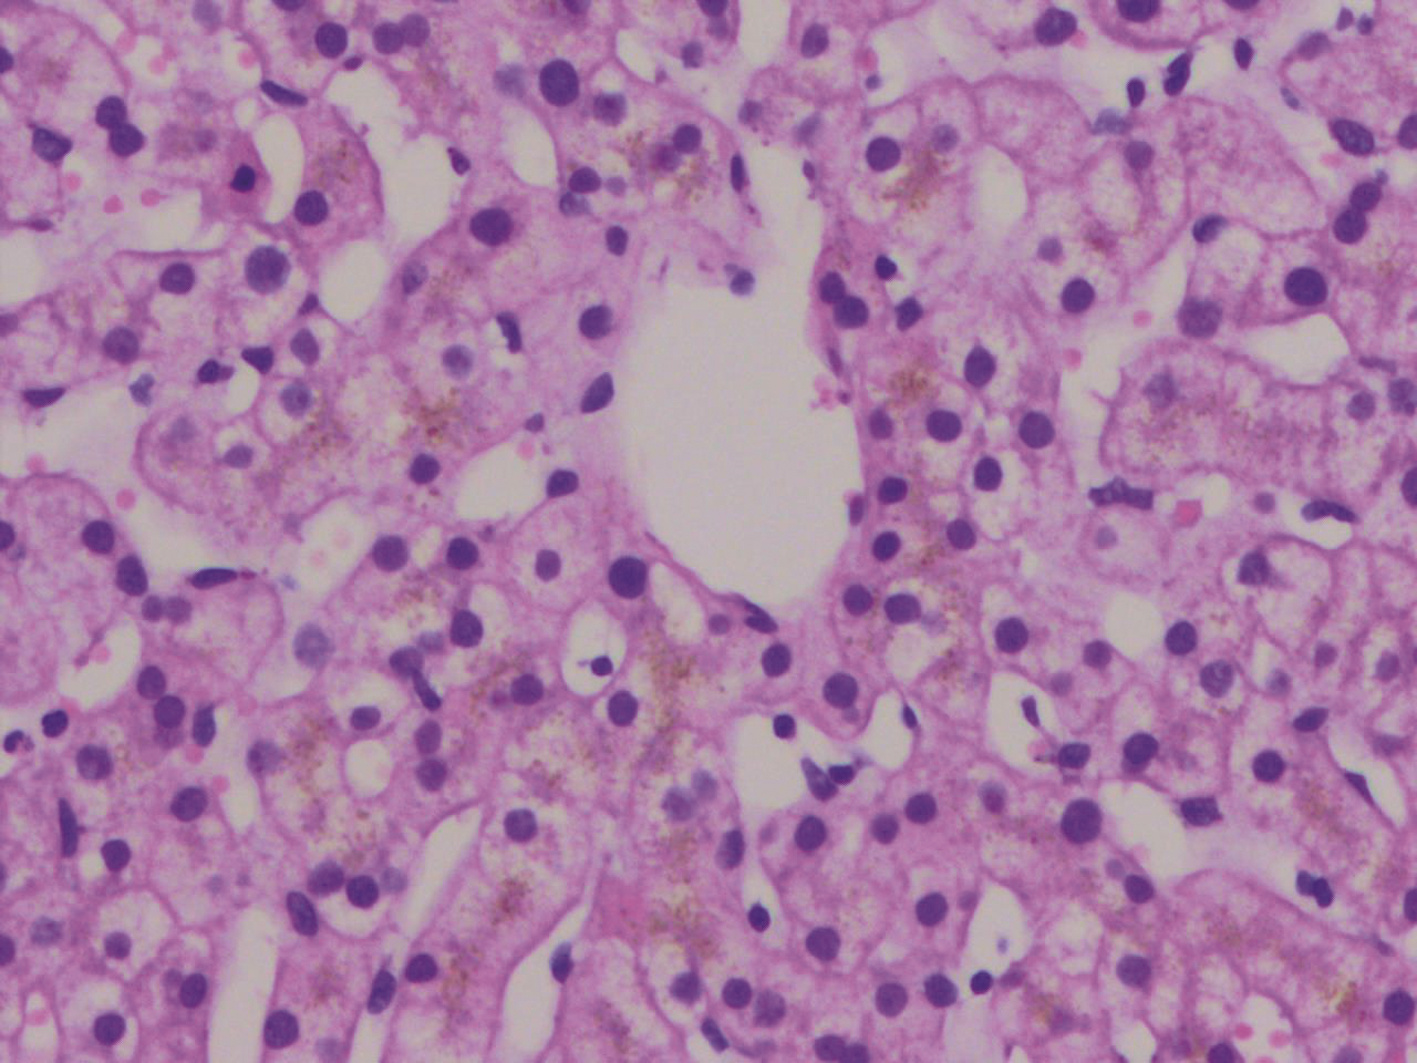

IgG4相关肝胆胰疾病诊疗进展

王天琪, 刘燕鹰

2022, 38(4): 762-766. DOI: 10.3969/j.issn.1001-5256.2022.04.006

摘要(1920) HTML (362) PDF (1911KB)(231)

摘要:

IgG4相关肝胆胰疾病是IgG4相关疾病多器官纤维化炎性疾病的一部分,包括IgG4相关自身免疫性胰腺炎、IgG4相关硬化性胆管炎、IgG4相关肝脏病变。主要病理表现为IgG4+浆细胞、淋巴细胞浸润,伴有席纹状纤维化、闭塞性静脉炎和嗜酸性粒细胞浸润。临床诊断多采用IgG4相关疾病综合诊断标准和专科制定的特异性器官受累诊断标准,难点在于与肿瘤性疾病的鉴别,新型诊断标志物有望提高诊断敏感度及特异度。迄今,一线治疗药物仍为糖皮质激素,生物制剂,尤其是CD20单抗疗效肯定,对于激素禁忌/不耐受或复发难治性患者不失为一种选择。